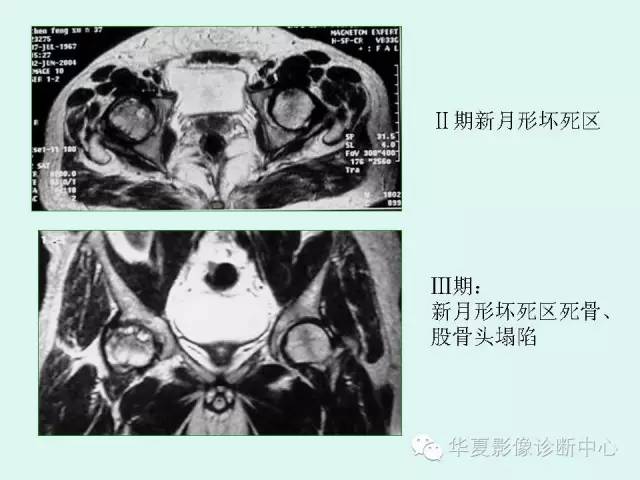

【PPT】股骨头缺血性坏死